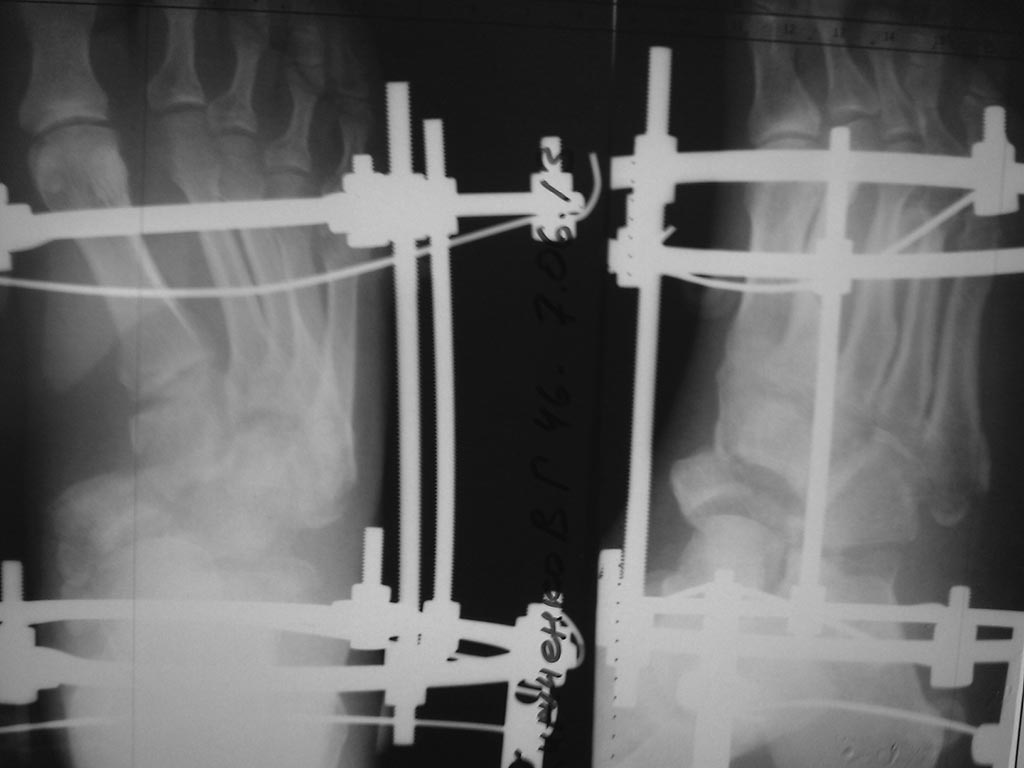

как-то так, извиняюсь за снимки, дистрактор все же пригодился, проблем с вправлением не было. На предыдущие вопросы, травма - по ноге проехал УАЗ, не курит, не злоупотребляет.

Здравствуйте! Может снимки повторить?

По тем, что есть вроде ситуация стала получше.

А почему такой выбран метод фиксации? вроде советовали спицами. И пластина как-то уж больно далеко от костей. Еще если можно фото после операции.